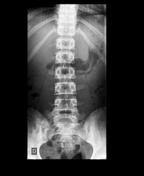

Thoracolumbar Spine X Rays from dontforgetthebubbles.com However, since tpfs can also occur due to repetitive loading, this underreporting may be quite significant(8). Possible causes, signs and symptoms, standard treatment options and means of care and support. There is a strong association between transverse process fractures and other traumatic injuries. A transverse process fracture is considered as a rare injury. A fracture of a transverse processis a break of a part of one of the bones in the spine. Vertebral artery angiography, performed in eight patients with fractures involving the transverse foramen, showed dissection or occlusion of the vertebral artery in seven (88. Transverse processes are used as lever arms by the deep spinal muscles to maintain posture and to induce rotation and lateral bending. This may be done through diet and exercise.

Fractures Of The Thoracic And Lumbar Spine Orthoinfo Aaos from orthoinfo.aaos.org There is one on both sides of every vertebra in the… a transverse process fracture is quite a rare injury. A transverse process fracture is a break in 1 or more transverse process. Transverse process fracture is a rare and stable fracture of the spine. We retrospectively reviewed the reports of lumbar spine and abdominopelvic ct scans from 2017 and 2018 to classify the types of spine fractures, their mechanism of injury, treatment and. This may be done through diet and exercise. Transverse process fractures caused by stress are likely under detected since even an acute transverse process fracture requires a high index of suspicion to be correctly identified(4,7). Thoracic transverse process fractures (ttpfs) are injuries that go unnoticed during traditional autopsies, as demonstrated by a lack of medicolegal publications regarding ttpfs. Transverse processes are typically fractured in direct blows from athletics touch or impact from falls from bikes/motorbikes or by heights.

Transverse Process Archives Md Direct from i0.wp.com Transverse processes are typically fractured in direct blows from athletics touch or impact from falls from bikes/motorbikes or by heights. A transverse process fracture is considered as a rare injury. A transverse process fracture is a break in 1 or more transverse process. Transverse process fracture you have fractured a transverse process. Transverse process fractures are common sequelae of trauma, although they are considered a minor and stable lumbar spine fracture. Care guide for transverse process fracture. You have fractured a transverse process. Transverse process fracture is a rare and stable fracture of the spine.